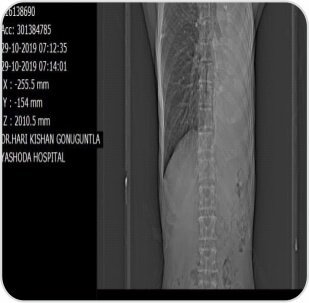

Pre procedure CT image showing collapsed left lung with occluded left main bronchus